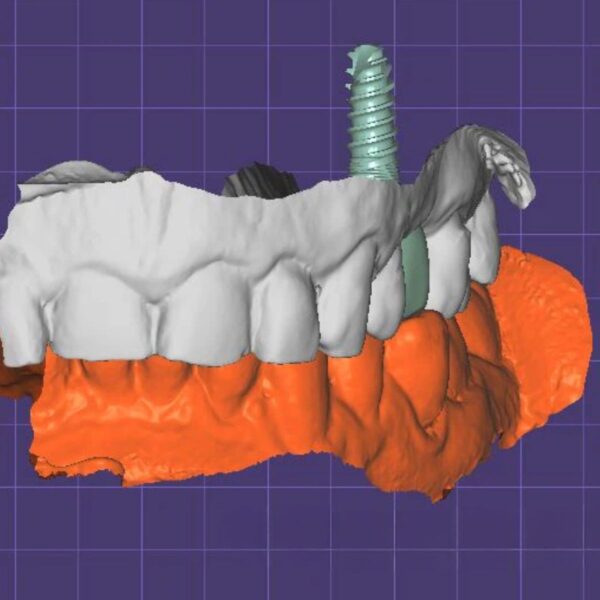

China Dental Design Complex Case Gallery

Challenging Projects That Showcase Our China Dental Design Expertise

Implant Crown Design

- Multi-unit implant bridges

- Surgical guide integration